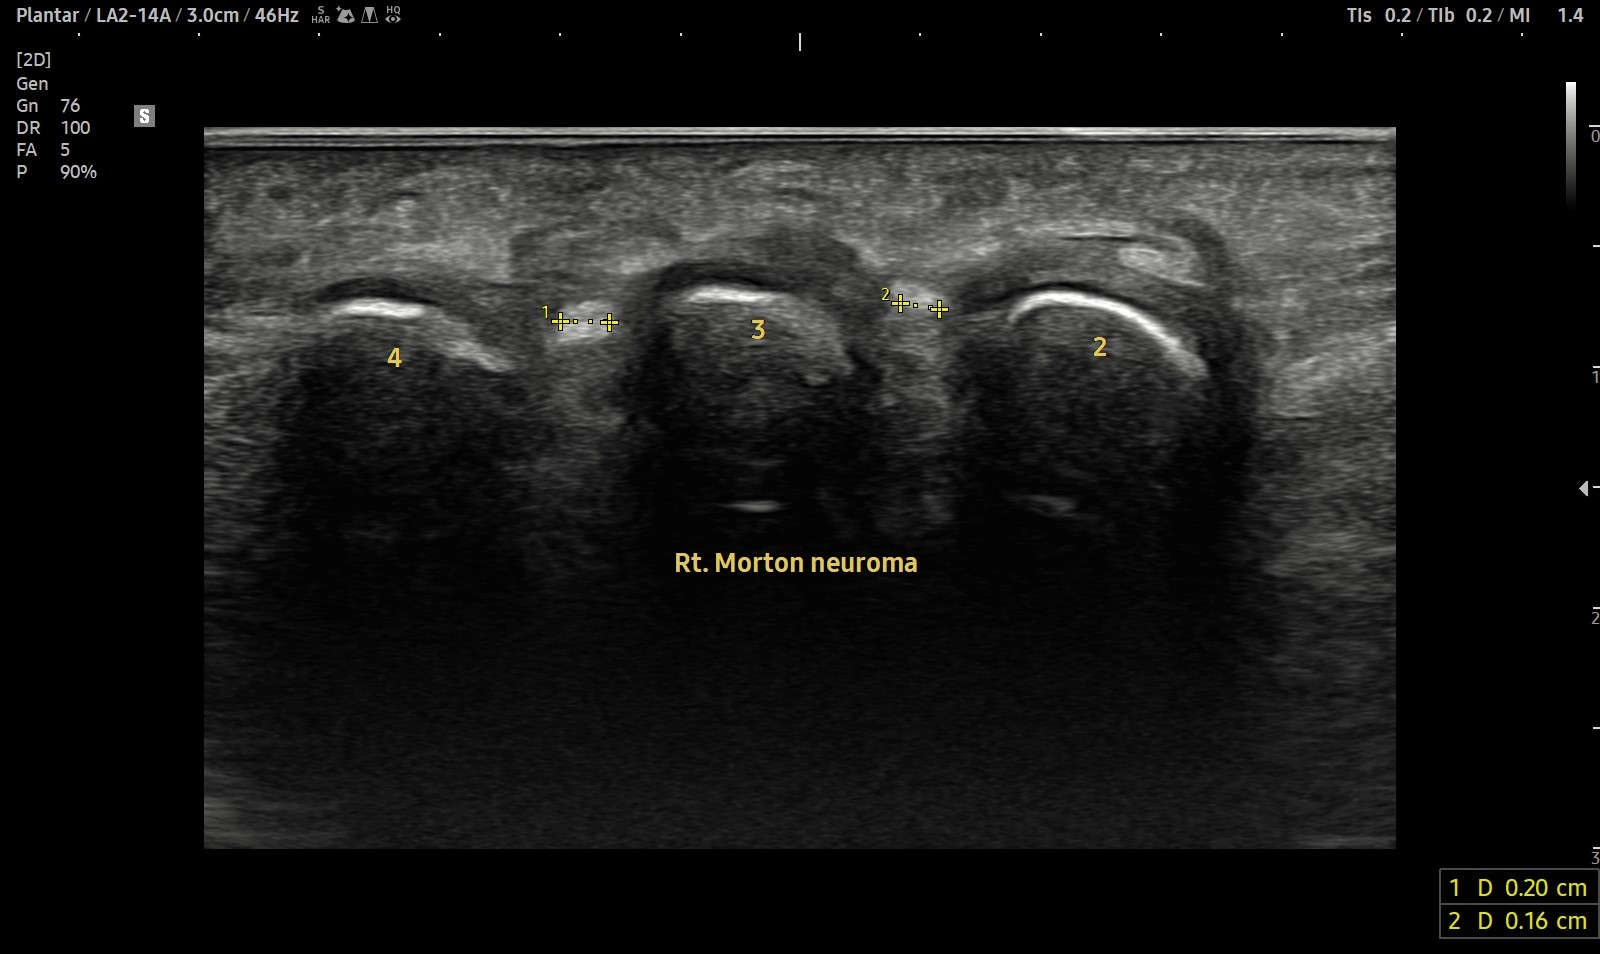

- 치료기간 : 2025. 5 . 7 ~ 2025 . 7 . 12

- 치료횟수 : 10 회 ( 2 cycle )